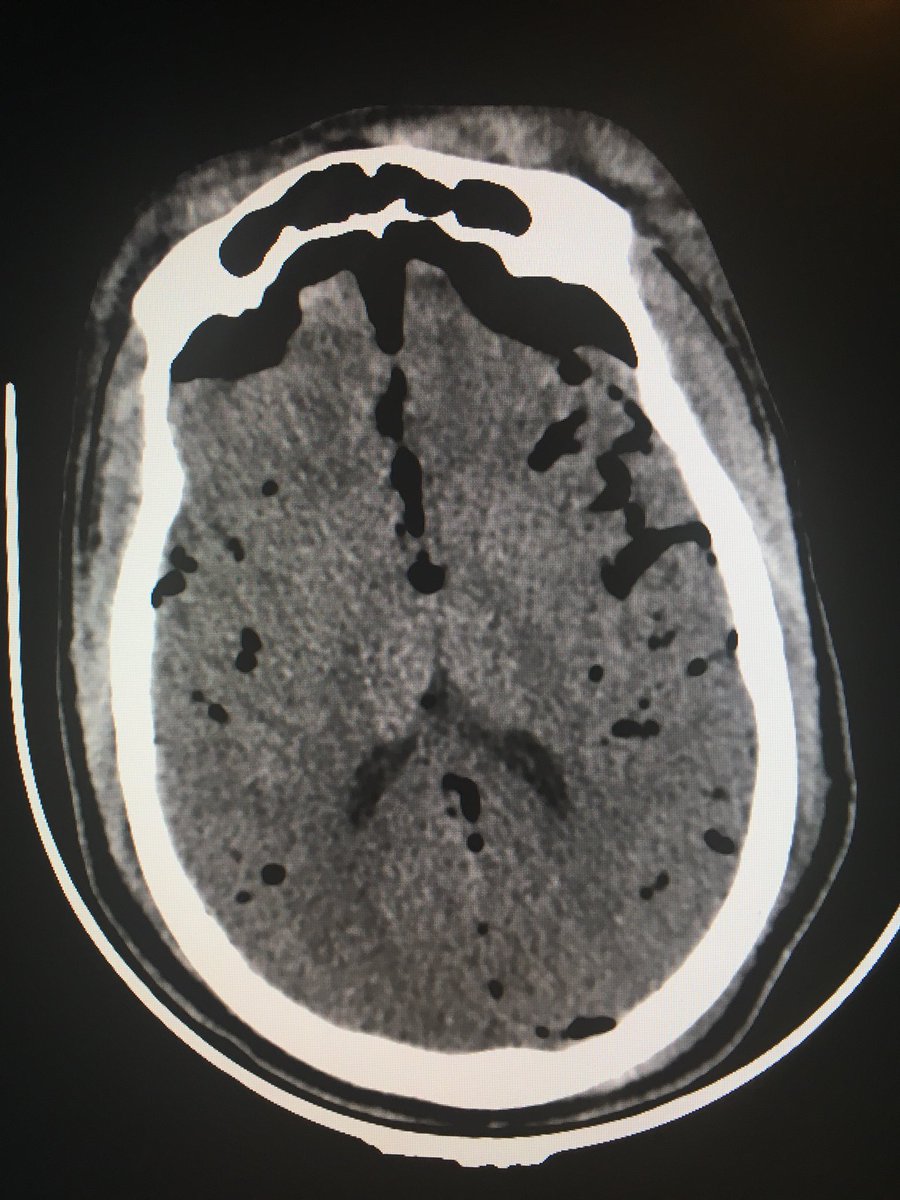

Mount Fuji Sign Radiology

Mount Fuji Sign Is Seen On Cross Sectional Imaging And Implies Tension Pneumocephalus Is Present The Sign Refers To The Pres Radiology Frontal Lobe Vp Shunt

Hanno Pretorius On Twitter Correct Answer Is Indeed Mount Fuji Sign After The Famous Volcano In Japan Indicative Of Tension Pneumocephalus Requires Urgent Neurosurgical Intervention Another Case Next Week Emergencyradiology Empret 1 Biginjapan

The Mount Fuji Sign Radiology

The Mount Fuji Sign Nejm